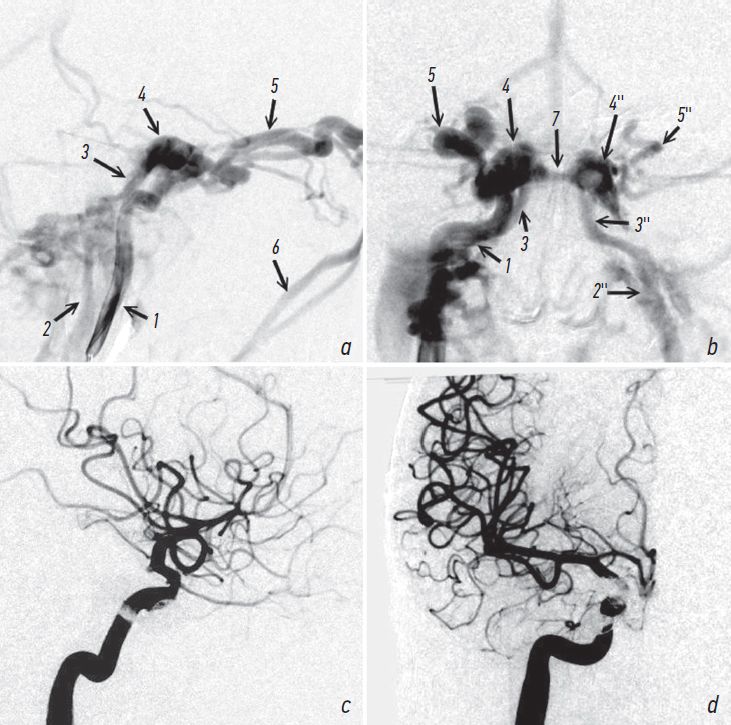

При селективной церебральной АГ верифицировано функционирующее ККС в правом кавернозном синусе с полным сбросом. Отток происходит в расширенные глазные вены справа и нижние каменистые синусы с обеих сторон путём перетока по межкавернозным анастомозам (рис. 5, a, b). Мультиспиральная компьютерная томография не выполнялась вследствие установления диагноза по данным церебральной АГ.

Рис. 5. Посттравматическое каротидно-кавернозное соустье справа. Ангиография правой внутренней сонной артерии до (а, b) и после эндоваскулярной операции (c, d) — полное разобщение фистулы. 1 — правая внутренняя сонная артерия; 2, 2'' — правая и левая внутренние яремные вены соответственно; 3, 3'' — правый и левый нижние каменистые синусы; 4, 4'' — правый и левый кавернозные синусы; 5, 5'' — правая и левая верхние глазные вены; 6 — правая лицевая вена; 7 — задний межкавернозный синус

Fig. 5. Right post-traumatic carotid cavernous fistula. Angiography of the right internal carotid artery before (a, b) and after endovascular treatment (c, d) — complete obliteration of the fistula. 1 — right internal carotid artery; 2, 2'' — right and left internal jugular veins; 3, 3'' — right and left inferior petrosal sinuses; 4, 4'' — right and left cavernous sinuses; 5, 5'' — right and left superior ophthalmic veins; 6 — right facial vein; 7 — posterior intercavernous sinus

Пациенту проведена эндоваскулярная операция трансартериальным и трансвенозным доступом: фистула располагалась в горизонтальном сегменте сифона. Под рентгенологическим контролем в правую ВСА установлен проводниковый катетер. На уровень фистулы подведён баллон-катетер. Через фистулу в передний отдел синуса заведён микрокатетер для доставки спиралей. Баллон раздут до полной окклюзии ВСА на уровне фистулы, через микрокатетер начата установка микроспиралей в кавернозный синус. Часть спиралей вывихивалась в просвет ВСА, в связи чем они были извлечены. Принято решение произвести трансвенозную катетеризацию синуса. Пунктирована правая бедренная вена, установлен интродюсер. Второй проводниковый катетер заведён в устье правого нижнего каменистого синуса. Катетеризирован задний отдел кавернозного синуса, в синус установлены четыре микроспирали. При контрольной АГ фистула продолжала функционировать. Для предотвращения просачивания крови между витками спирали введено 0,5 мл эмболизирующего материала Squid 18. При контрольной АГ задний отток не контрастируется, однако фистула продолжает функционировать с передним оттоком. Решено перейти на артериальный доступ. Вновь катетеризирован синус через фистулу и при раздутом баллоне имплантирована одна микроспираль. При контрольной АГ выявлено, что фистула выключена из кровотока тотально (рис. 5, c, d).